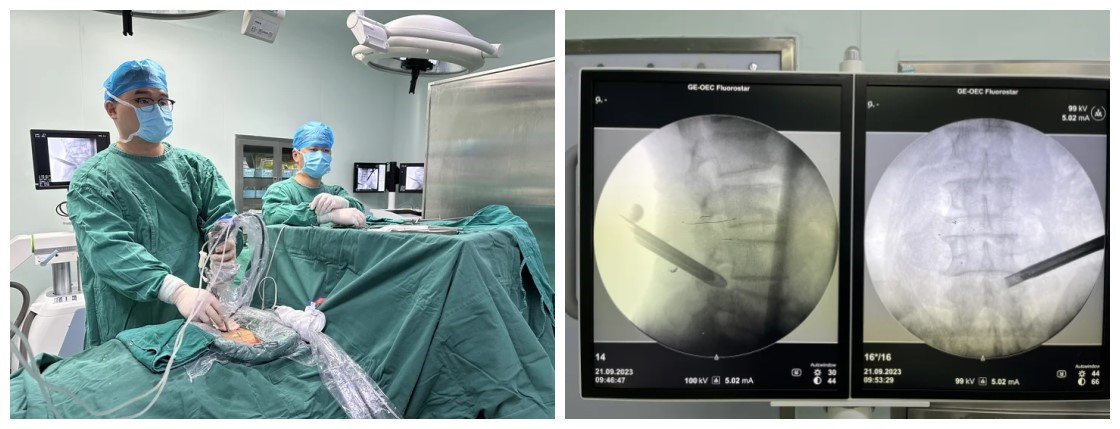

(1)微创精准化:大力发展并成熟应用脊柱内镜(椎间孔镜/椎间盘镜)、微创通道下减压融合术(MIS-TLIF)、经皮椎弓根螺钉内固定等前沿微创技术,以最小创伤解决患者病痛。